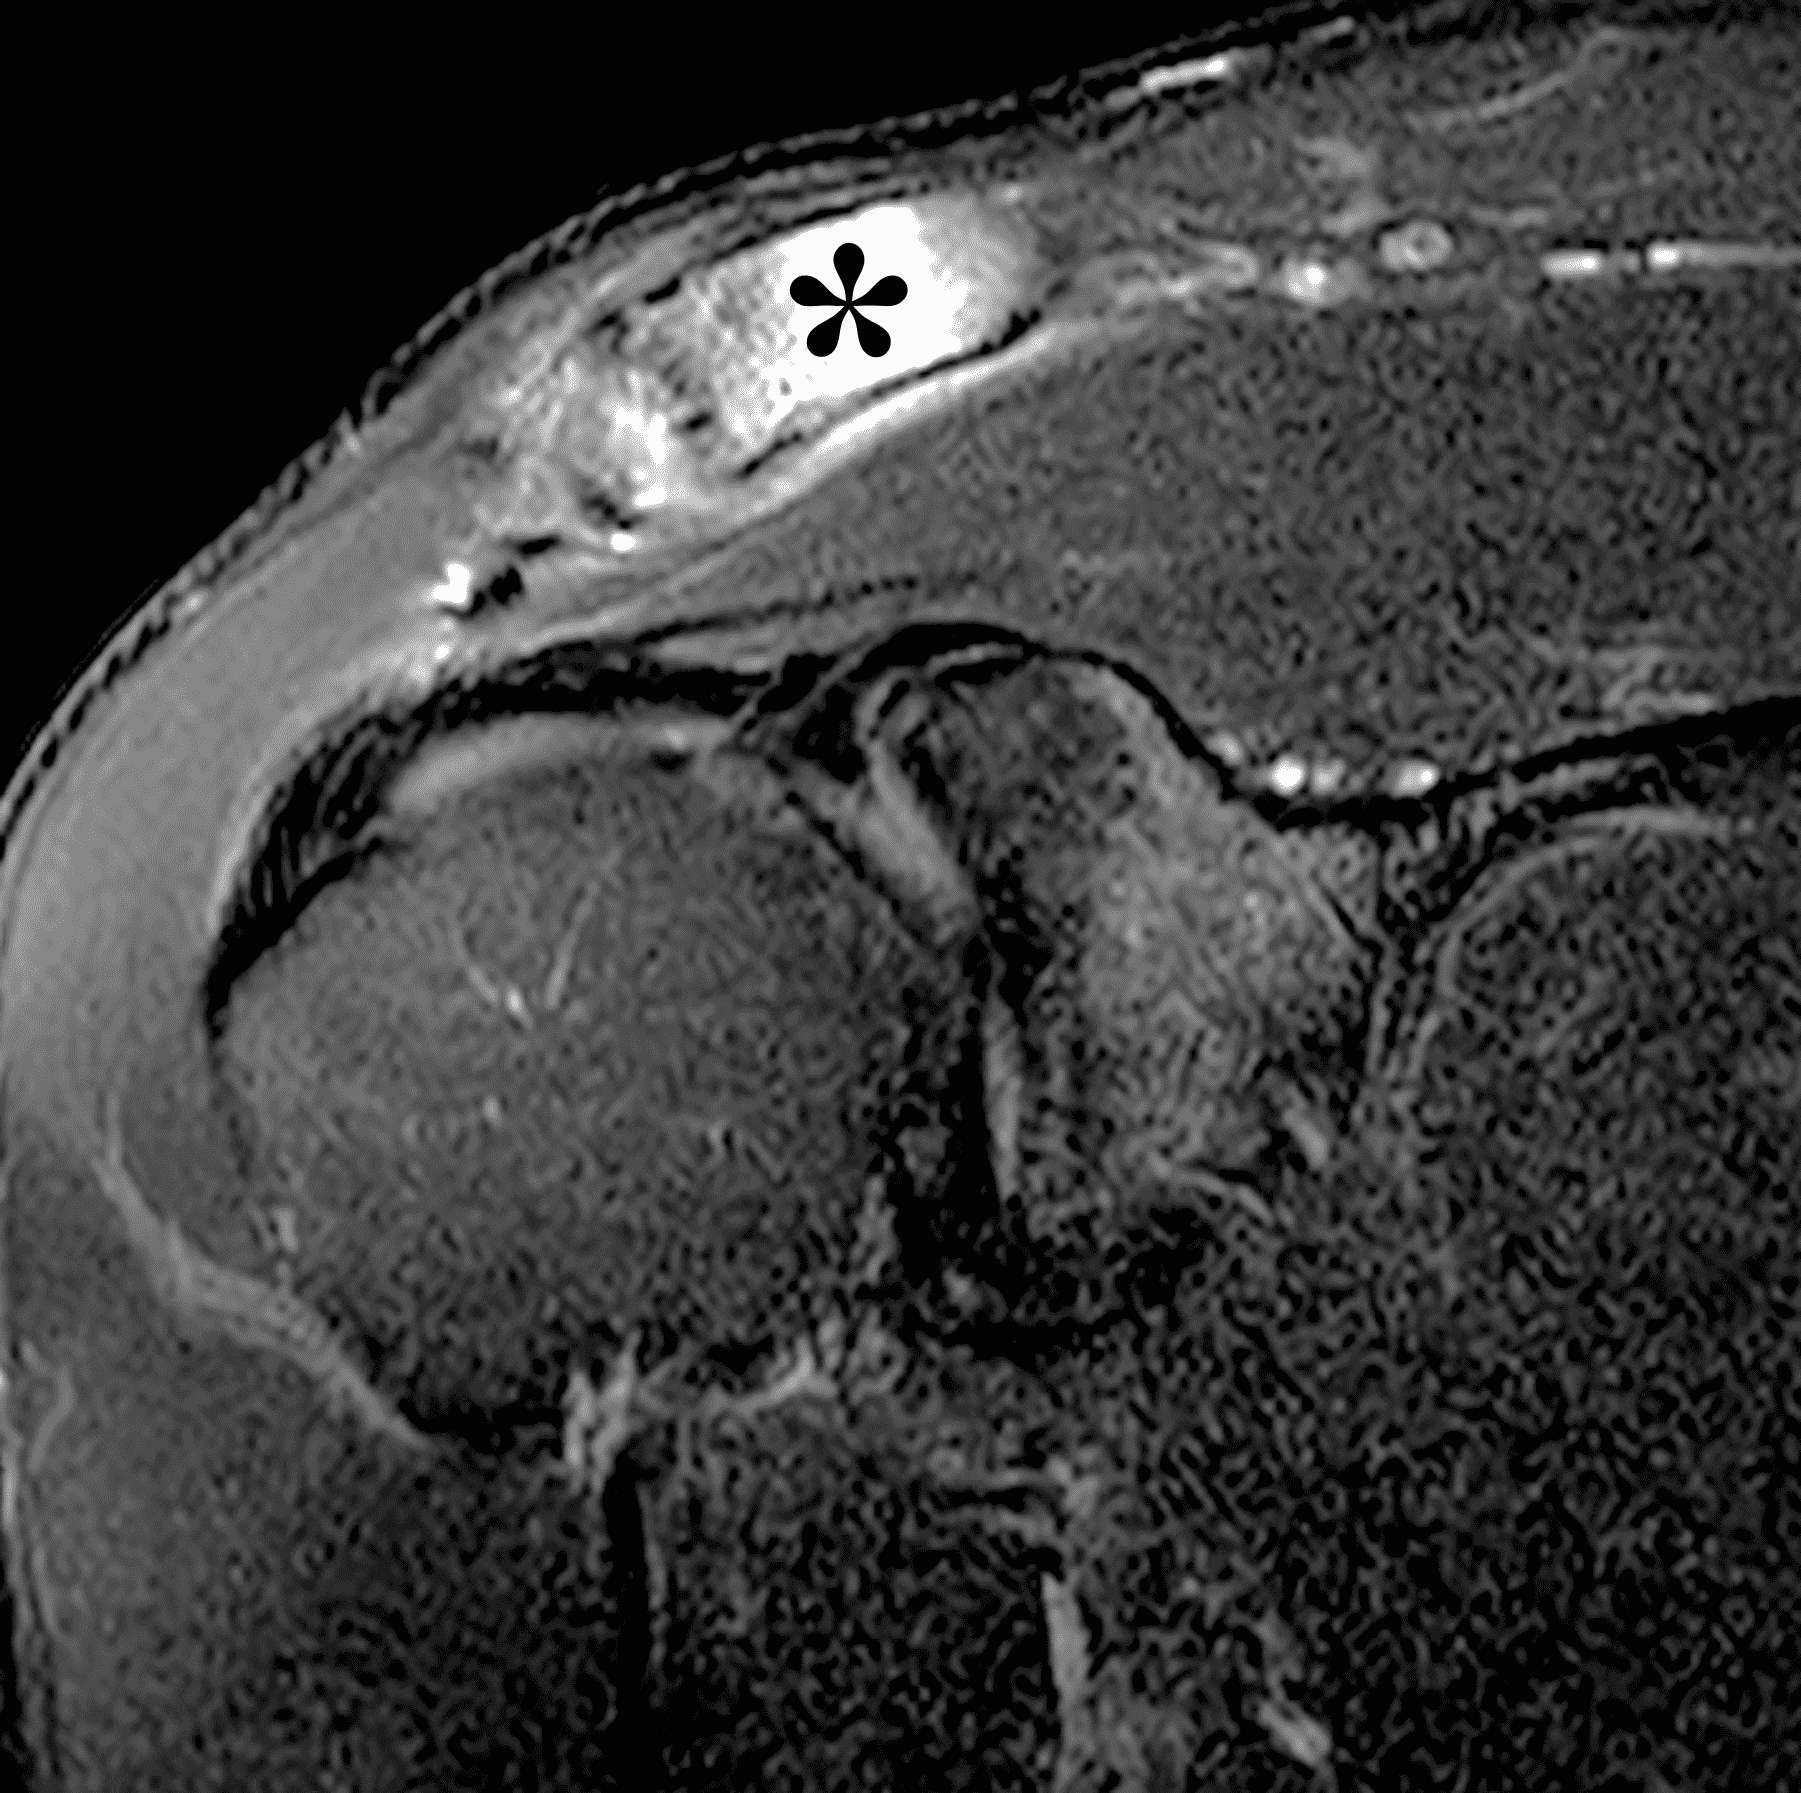

A 49-year-old male, avid weightlifter complains of chronic pain along the superior aspect of his right shoulder. He denies acute trauma. An AP radiograph (Figure 1A), as well as oblique coronal SPAIR (Figure 1B), axial fat-suppressed fluid sensitive (Figure 1C), and oblique sagittal T2-weighted images (Figure 1D) are shown. What are the findings? What is your diagnosis?

The principle MRI finding of DCO is distal clavicular marrow edema and surrounding inflammation on fluid-sensitive pulse sequences, especially with fat suppression (Figures 3 and 4).2, 9 Marrow changes can occur in patients with normal radiographs,10 in which case a term like “stress/overuse related marrow edema,” might be preferable to “osteolysis.” On MRI, more severe cases may show erosions or cysts in the distal clavicle and loss of the subchondral bone plate in addition to more pronounced marrow and soft tissue edema. A band of low signal paralleling the distal bone end may be present, suggesting a stress fracture line (Figure 5).8 However, a similar appearance can be due to the sclerotic rim surrounding distal clavicle cysts or small erosions (Figure 6). A small effusion or mild synovitis is often present in the AC joint.  Soft tissue edema within and surrounding the AC joint capsule and distal clavicular periosteum may be visible (Figure 3).  Some patients may also show marrow edema (or even erosions) in the anterior acromion, but the changes are typically more severe in the distal clavicle (Figures 5 and 7).2